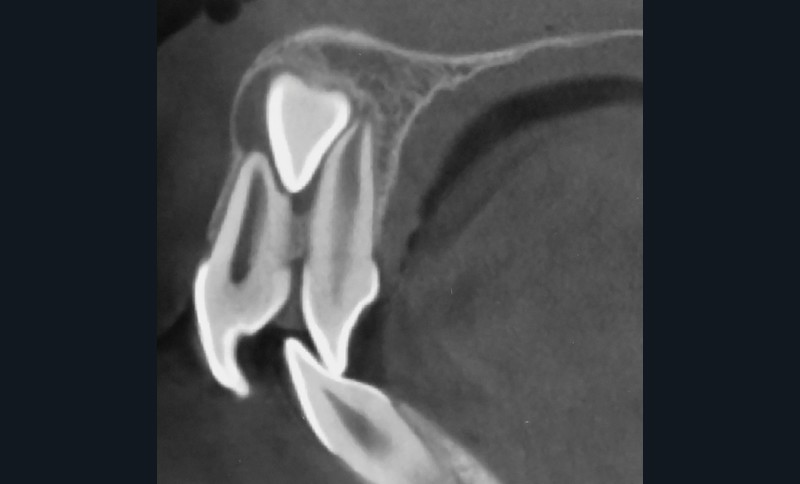

Dans un premier temps, l’extraction des 11 et 21 est réalisée. Un bouton est collé sur la 13, visible dans l’alvéole de la 11 afin de permettre sa désinclusion (fig. 2). La traction se fait à l’aide d’un arc TMA .016 x .022 en overlay afin d’avoir un axe de traction horizontal et vestibulaire évitant une résorption de la 12 à cette étape (fig. 3a,b) [3]. Ne pouvant pas mettre d’arc de Nance du fait de la position palatine des incisives latérales, il est convenu que des minivis d’ancrage peuvent être nécessaires si une perte d’ancrage postérieure est constatée (ce qui n’est pas le cas).